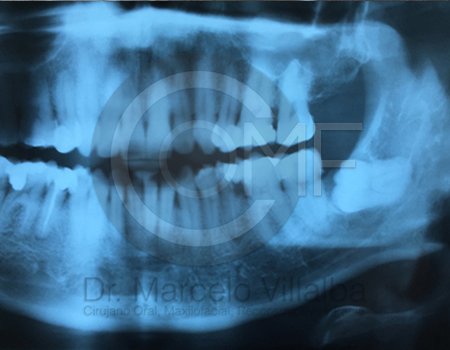

Contenido Sensible y Gráfico

Si usted no pertenece al área de la salud, las imágenes pueden ser muy explícitas.